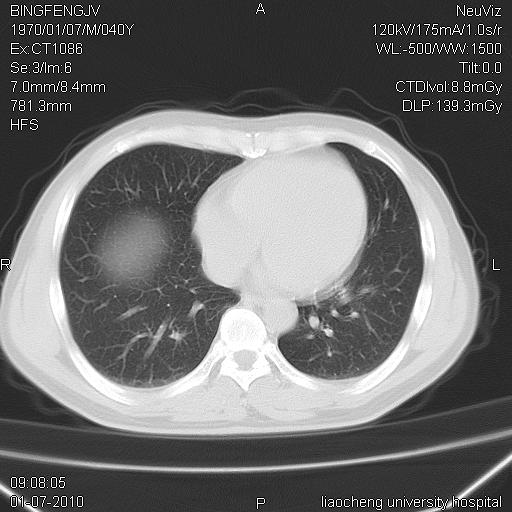

标题: CT23764B:男 40 肺部CT [打印本页]

标题: CT23764B:男 40 肺部CT

治疗2周后

炎症性病灶,继发性改变。

考虑左肺上叶近胸膜下炎症并肺气囊形成。

炎症,大部吸收。